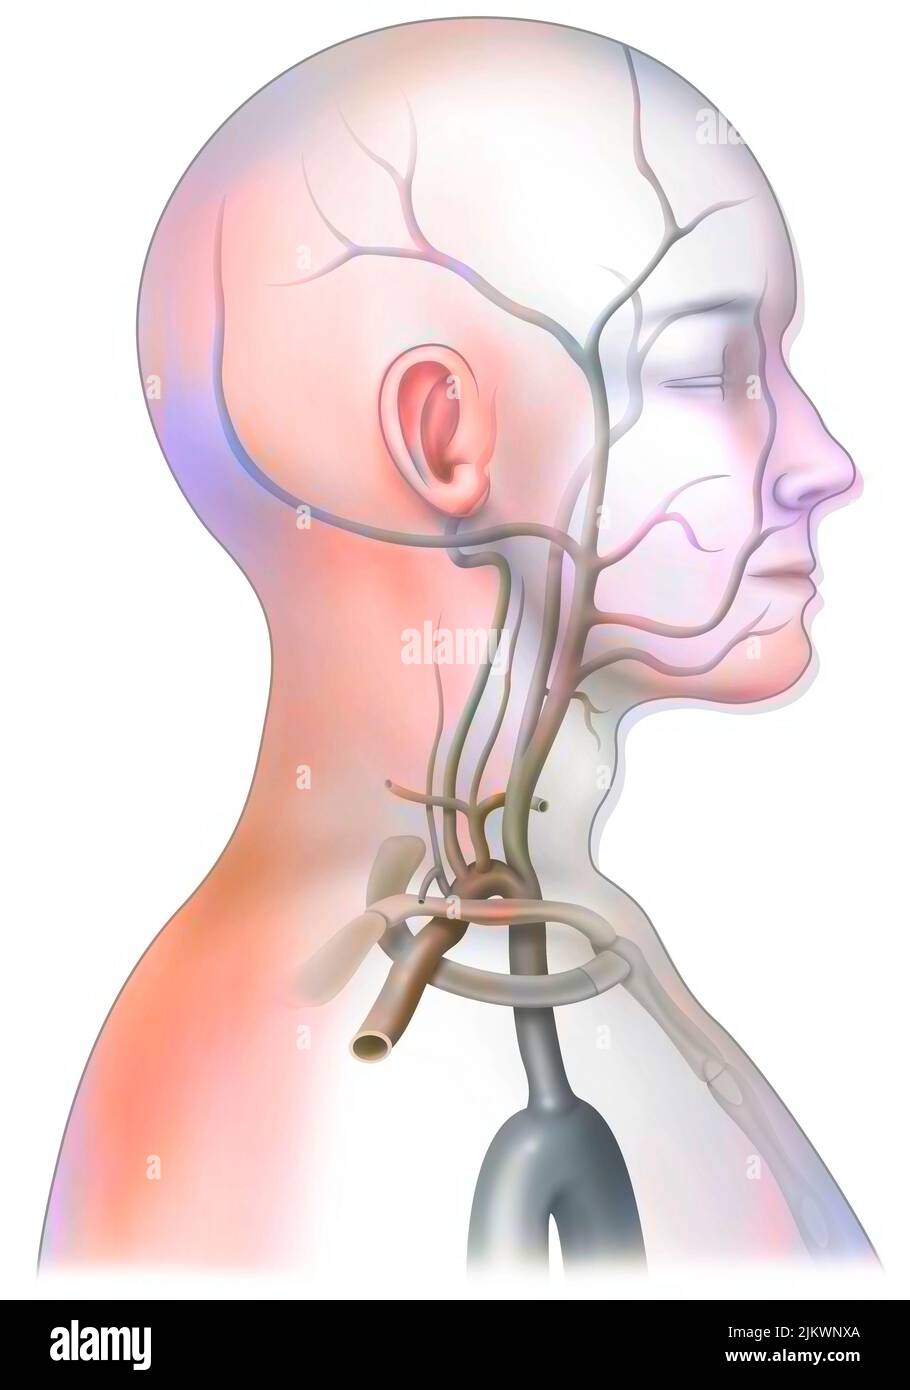

RM2BE1154–Medizinische Radiologie mit einem normalen linken Halsschlagader. Die gemeinsame Halsschlagader versorgt Hals und Kopf mit sauerstoffreichem Blut.

RM2BE0J9D–Medizinische Radiologie mit einem normalen linken Halsschlagader. Die gemeinsame Halsschlagader versorgt Hals und Kopf mit sauerstoffreichem Blut.

RF2SGJF65–Anatomische Darstellung der zerebralen Durchblutung. Das Blut gelangt durch die Arterien der Karotis und der Wirbelsäule in das Gehirn und liefert Sauerstoff und Nährstoffe.